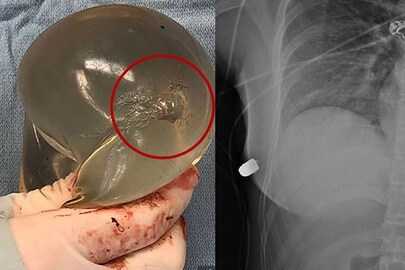

മാറിൽ വെടിയേറ്റ യുവതി രക്ഷപ്പെട്ടത് അത്ഭുതകരമായി. ഹൃദയം തുളച്ചുകടന്നുപോകുമായിരുന്ന വെടിയുണ്ടയെ ദിശതിരിച്ചുവിട്ടത് യുവതി ധരിച്ച കൃത്രിമ സ്തനമായിരുന്നു എന്നതാണ് രസകരം. ദിശതെറ്റിയ വെടിയുണ്ട കാര്യമായ ജീവഹാനി വരുത്താതെ ശരീരത്തിൽ തളച്ചു.

യുവതി ധരിച്ചിരുന്ന കൃത്രിമ സ്തനമാണ് ജീവൻ രക്ഷിച്ചതെന്ന് ഡോക്ടർ പറഞ്ഞു. സിലിക്കോൺ സ്തനത്തിന് വെടിയുണ്ടയേറ്റ് കേടുപാട് പറ്റിയ ചിത്രവും എക്സ്റേ ചിത്രവും പുറത്തുവിട്ടിട്ടുണ്ട്. ശസ്ത്രക്രിയയിലൂടെ ശരീരത്തിൽ തളച്ച വെടിയുണ്ട നീക്കി.